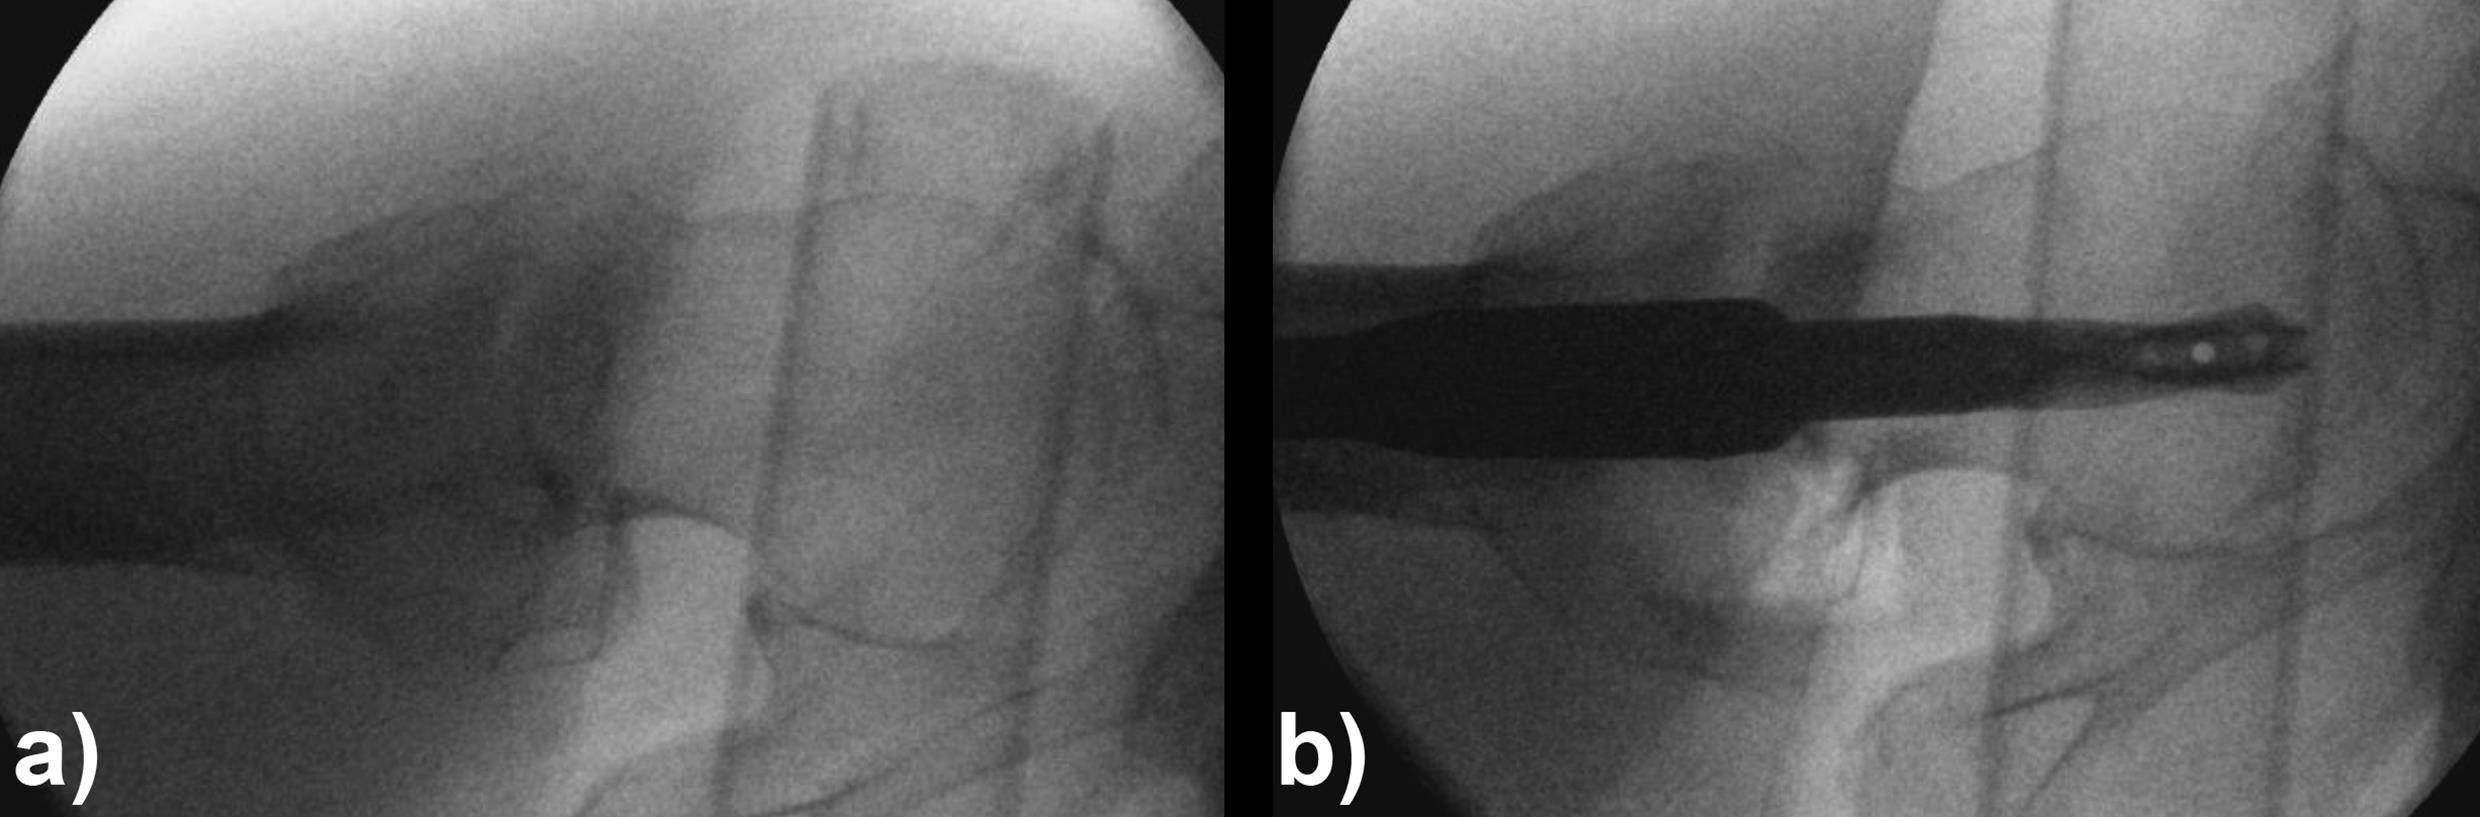

An 83-year-old female patient sustained a 31-A.2.2 fracture of the right proximal femur after a fall at home (Figs 1-2). Intraoperative and postoperative images are shown (Figs 3-5).

Case provided by Michael Blauth, Innsbruck, Austria